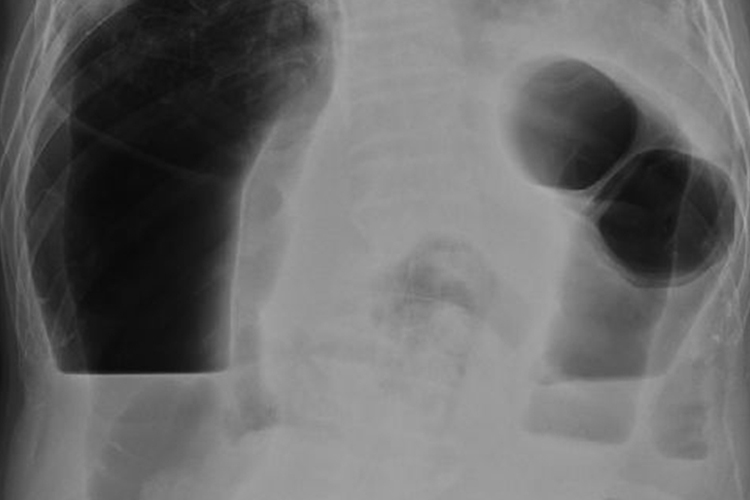

肠梗阻的X线表现为肠腔内气体影,立位或卧位摄片可见液平面及胀气肠襻。同时患者可伴有腹痛、呕吐、腹胀等症状。

一般在肠梗阻发生4-6小时后腹部X线摄片可显示出肠腔内气体影,立位或卧位摄片可见液平面及胀气肠襻。有时空肠黏膜环状皱襞可显示“鱼肋骨刺”状,结肠梗阻时胀气位于腹部周边,显示结肠袋形。如液平面呈阶梯状,则提示小肠梗阻。如显示“同心圆”X线征象时,应考虑肠套叠。